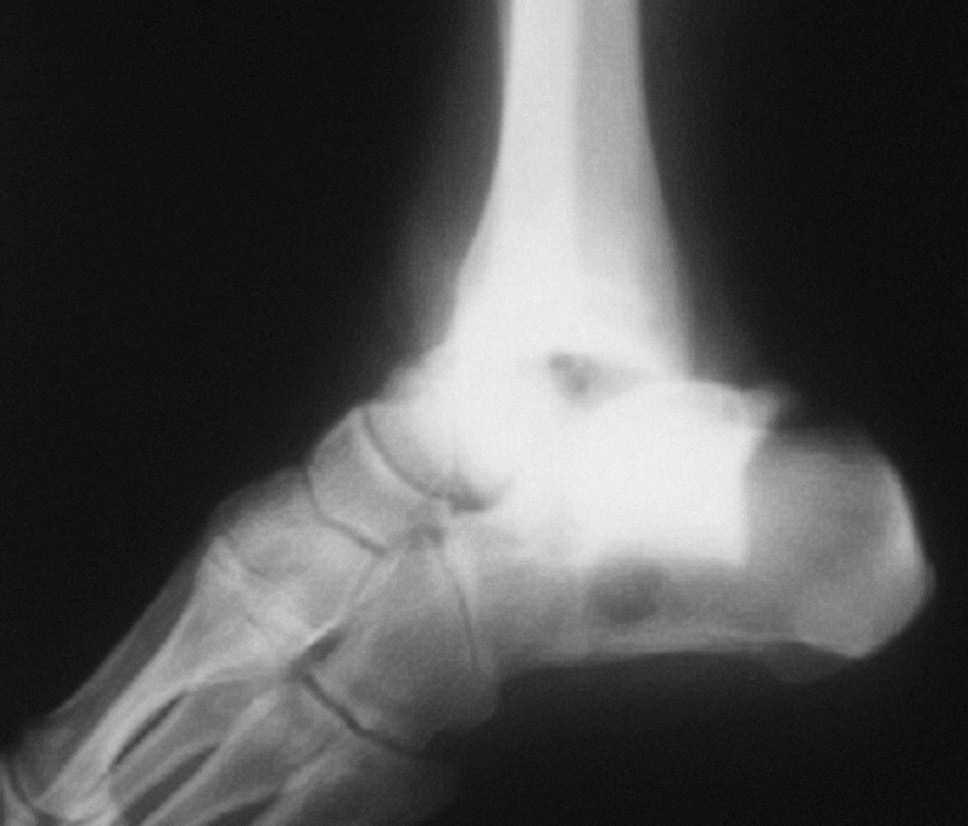

El seguimiento a la largo plazo de las fracturas del astrágalo identifica que la causa más común de los resultados pobres está asociada con la OA subastragalina, tibioastragalina y talonavicular, tanto en nuestra revisión, que alcanzó al 21% (8) de los casos (figs. 9 y 10), como en otros trabajos revisados15,17,19,22,23.

Fig. 9. --A) Fractura del cuerpo del astrágalo tipo B más rotura completa de los 3 ligamentos laterales del tobillo. B) Abordaje bilateral. Osteosíntesis. Sutura de ligamentos. Radiografía y tomografía computarizada a los 18 meses. Artrosis subastragalina y tibioastragalina.

Fig. 9. --a: Type B fracture of the astragalus with complete rupture of the 3 lateral ankle ligaments. b: Bilateral approach. Osteosynthesis. Ligament suture. Radiography and CT at 18 months. Sub-astragalar and tibio-astragalar arthrosis.

Fig.10. --Resultado a los 32 meses. 50° de BA. NAV del cuerpo y artrosis subastragalina y tibioastragalina

Fig.10. --Results at 32 months. BA 50º. Avascular necrosis of the astragalus and sub-astragalar and tibio-astragalar arthrosis.